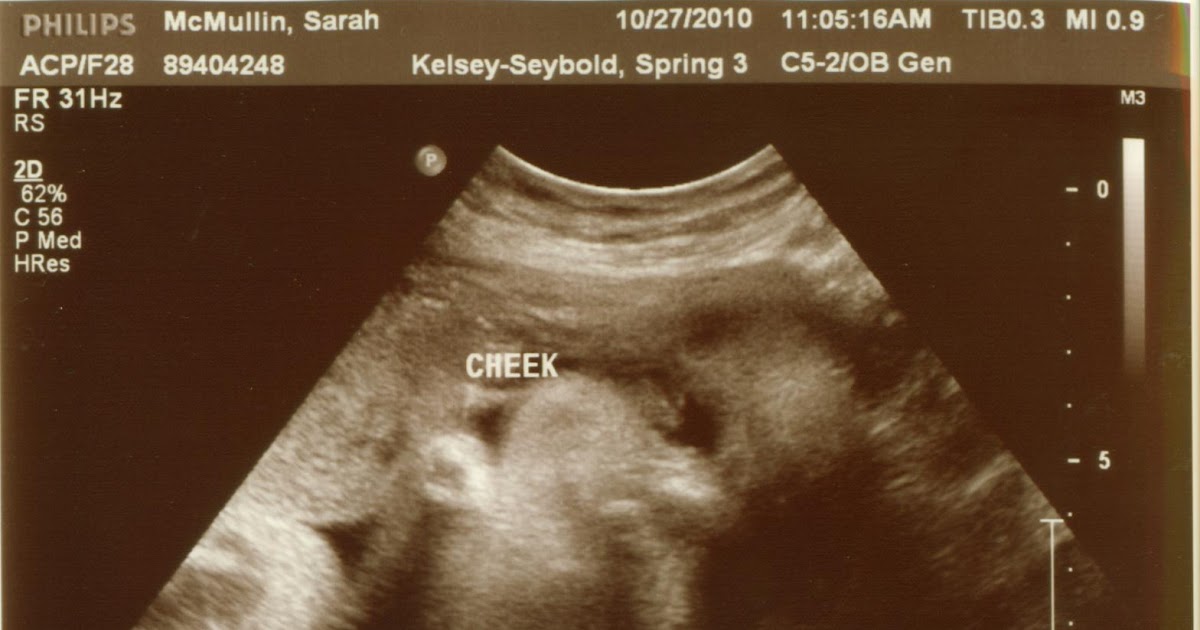

From www.thehahnstadts.com

The Hahnstadts Anatomy Scan + 21 Weeks Skeleton Face Ultrasound 3d ultrasound is an important tool for the evaluation of the fetal face in the first trimester. Using both multiplanar and surface. A transverse view of the head in the plane of the cavum septum. The different sutures and fontanelles are depicted in the coronal ( a ), superior ( b ), and lateral ( c ) views of the. Skeleton Face Ultrasound.